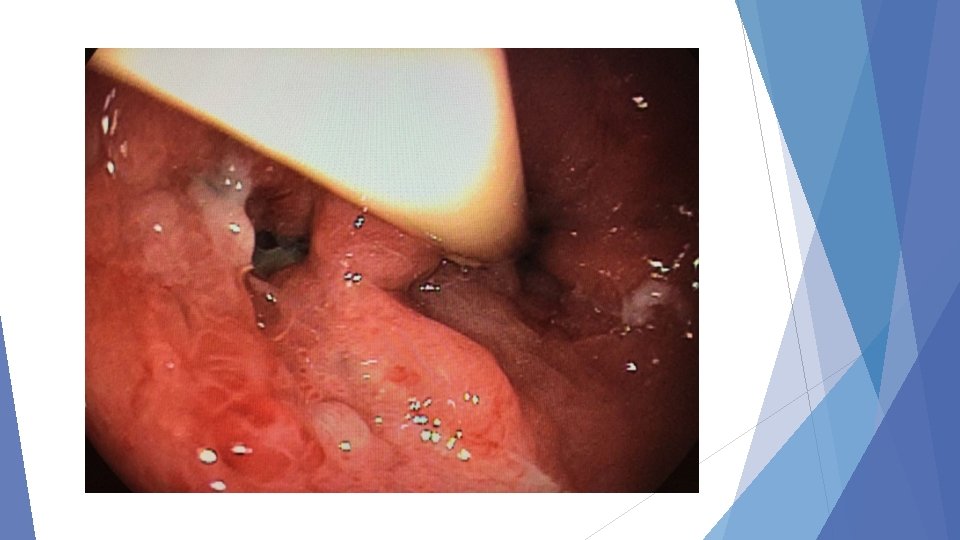

ESTENOSTOMIA E DILATAÇÃO ENDOSCÓPICA DIMINUIÇÃO DA LUZ GÁSTRICA

FÍSTULA

SEPTO LÚMEN GÁSTRICO FÍSTULA SÍTIOS DE INCISÃO DE SEPTOS